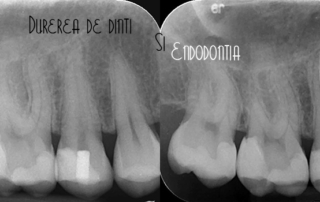

Dental pain and its treatment

Endodontics is a specialty of dental medicine that deals with the treatment of pulp or "dental nerve" disorders. The term "endodontics" derives from the Greek language from the words "endo" which means "inside" and "dont" which means tooth. Anatomically, the tooth has a dental crown and one or more dental roots. Inside the tooth we can find the pulp chamber (at the crown level) and the root canal (at the root level). The [...]